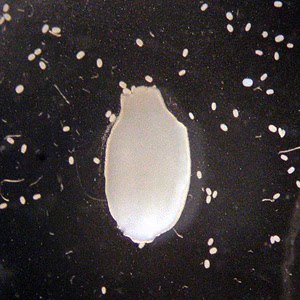

A mother found objects that she thought were maggots in the diaper of her 10-month-old child. She submitted the specimens to her state health department for identification and advice. Figures A and B show the submitted specimens using a low power dissecting microscope. The smaller white objects were released when one of the specimens was dissected, and two of the objects are shown in Figures C and D at 400× magnification using a compound microscope. These objects measured 200-250 micrometers and contained individual structures measuring approximately 40 micrometers. Digital images were captured and sent to DPDx for confirmation. What is your diagnosis? Based on what criteria?

Figure A